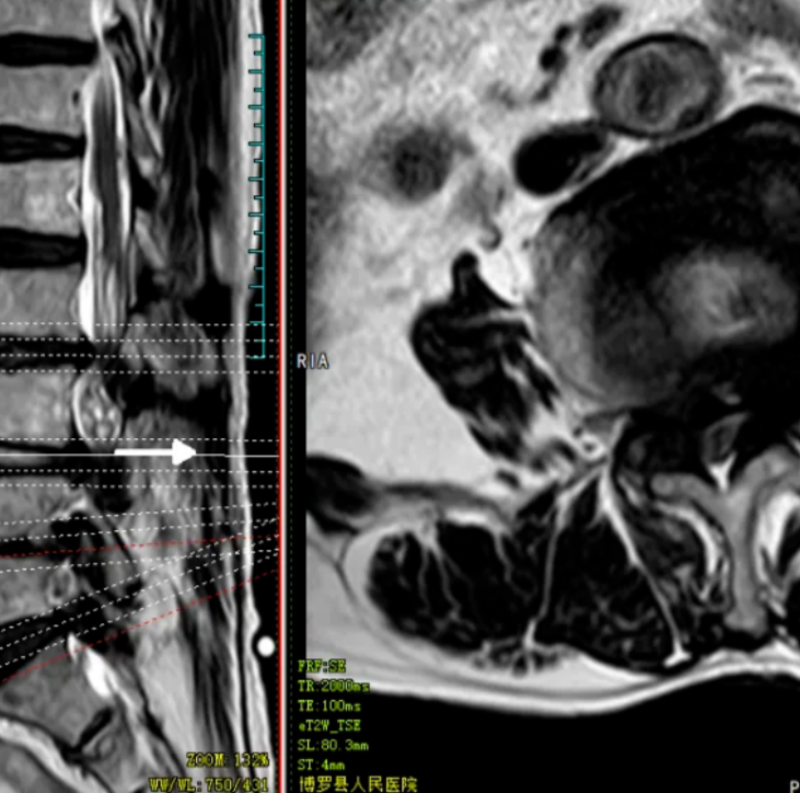

文章配圖

術前X線

術前CT

術前MRI

術后X線